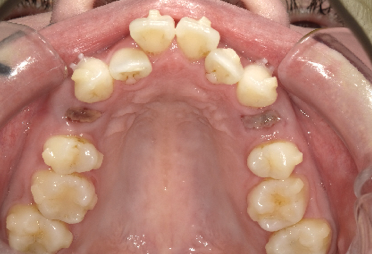

その時の状態がこちらです。

この状態で「様子を見ましょう」と言われた時のお母さんの気持ちは計り知れません。

不安に思われるのも当然だと思います。

当院では「すぐに矯正治療を開始しましょう」とお伝えしました。

初診時から治療を開始して約一年までの経過を比較してみます。

初診時から「様子を見ましょう」の指示に従い何もしなかった場合、将来的に確実に抜歯しての矯正が必要になっていたのではないかと考えられます。

お母さんが心配になって他でも話を聞いてみようを思ってくれたおかげで、このお子さんは一年後にはほぼキレイに歯が並んできました。

この子は今後も追加で治療が必要になる可能性はありますが、抜歯しての矯正は回避できたのではないかと考えています。